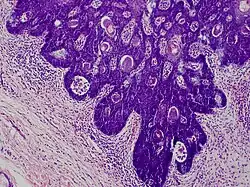

The typical histopathologic features of folliculosebaceous cystic hamartoma lesions are mesenchymal, follicular, and sebaceous elements; these lesions frequently manifest as sebaceous structures that emerge from a core infundibular cyst that is contained inside the dermis.[6] Mesenchymal alterations are frequently observed throughout the stroma and are characterized by fibrillary bundles of collagen with proliferating adipocytes, as well as a rise in capillaries and tiny venules.[7][6] There are clefts separating the neighboring dermis from the epithelial component.[6] In the stroma of lesions, immature adipocytes with lipid droplets and spindle- or starry-shaped nuclei have been observed; these cells are frequently located close to the sebaceous formations.[7]